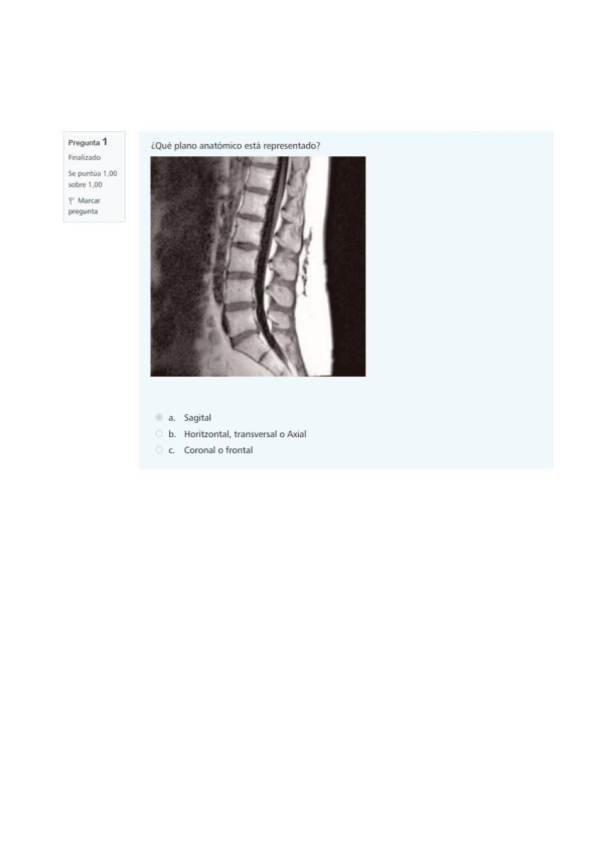

He publicado nuevos examenes de 1º Anatomía Humana: tipotestresuelto.pdf

33 páginas